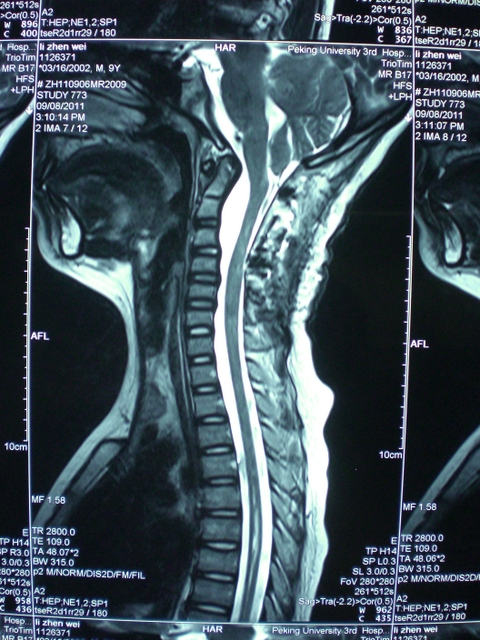

高颈段肠源性囊肿

高颈段肠源性囊肿高颈段肠源性囊肿